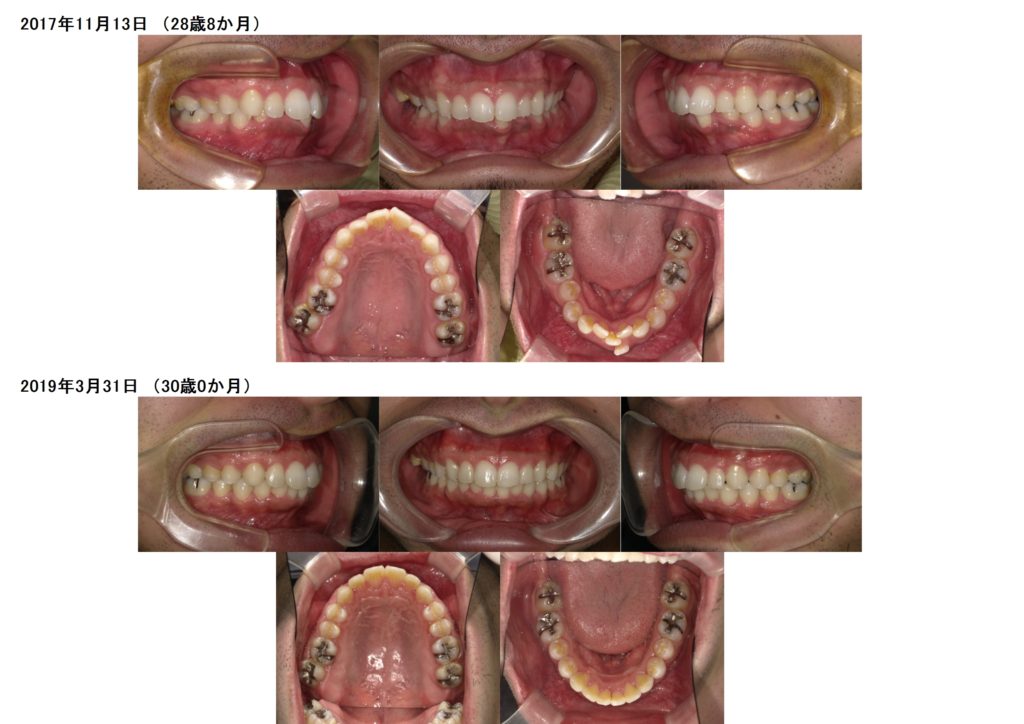

お口元が出ているのと、下の歯並びが気になるという事で、治療を開始しました。

上下の口腔内写真を見比べていただくと、約半年ほどで下のガタガタしていた歯並びが徐々に治っているのが分かると思います。

一年と少しで、下の歯のガタガタ、お口元、そして噛み合わせの深いところもしっかりと治りました。

ブラケットを外した時の患者様の笑顔は私たちスタッフも本当に自分のことのようにうれしくなります。